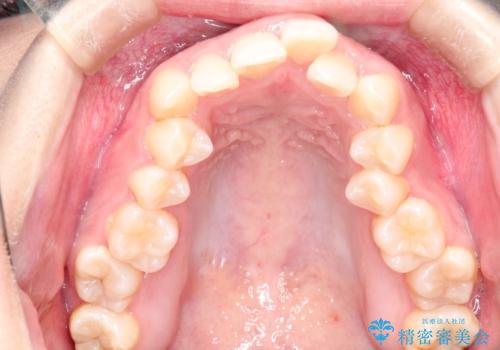

押しつぶされた歯列、アーチの拡大だけで非抜歯で改善した症例

初診時の歯並びの状態としては、上下ともに全体に及ぶの中等度以上のがたつき(叢生)があり、全額的に歯列のアーチが内側に押しつぶされた状態でした。

強い叢生がありましたが、抜歯は行わず上下顎ともに、主に歯列弓の拡大を行い叢生を改善しました。